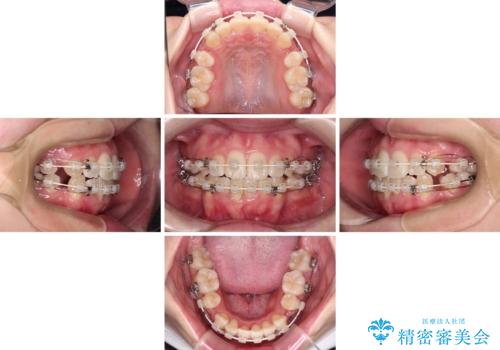

上下非接触で突出した前歯 ワイヤー装置による抜歯矯正

- 上下前歯の隙間と口元の出っ張った感じを気にして来院された患者様です。

上下の隙間は舌突出癖によるもので、またその癖により前歯が前方に出ている状態でした。

口元の出っ張りを改善するため、上下左右第一小臼歯4本を抜去し、ワイヤー装置にて矯正治療を行うこととしました。

舌の突出癖を改善するためのトレーニングをしっかりと行っていただいたことで、比較的スムーズに治療を進めることができました。

口元の突出感もしっかりと改善することができました。